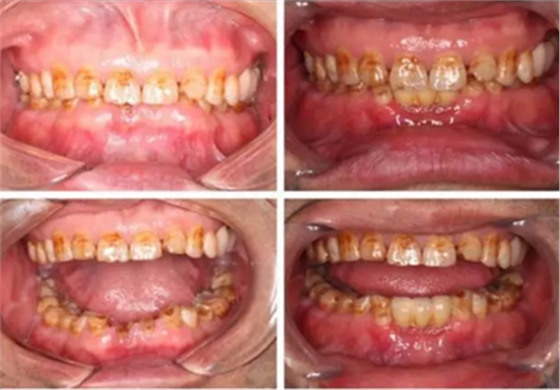

下圖是術(shù)前資料

患者,男性,47歲,全身情況良好,無手術(shù)禁忌,口內(nèi)因下前牙缺損松動(dòng)不美觀來院。初診檢查時(shí)發(fā)現(xiàn)患者前牙深覆合,下頜32、42缺失。31、41松動(dòng)二度,切緣磨耗嚴(yán)重,可探及髓腔,無保留價(jià)值。X-RAY檢查顯示:下頜前牙區(qū)寬度狹窄,咬合空間不足,無法行常規(guī)種植修復(fù).